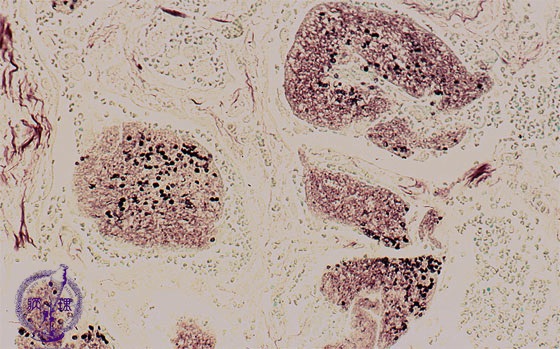

Microscopic view (Grocott stain, intermediate power view): On Grocott stain capsules of pneumocystis are round, cup or crescent shaped and 5 to 7um in diameter (smaller than an erythrocyte).